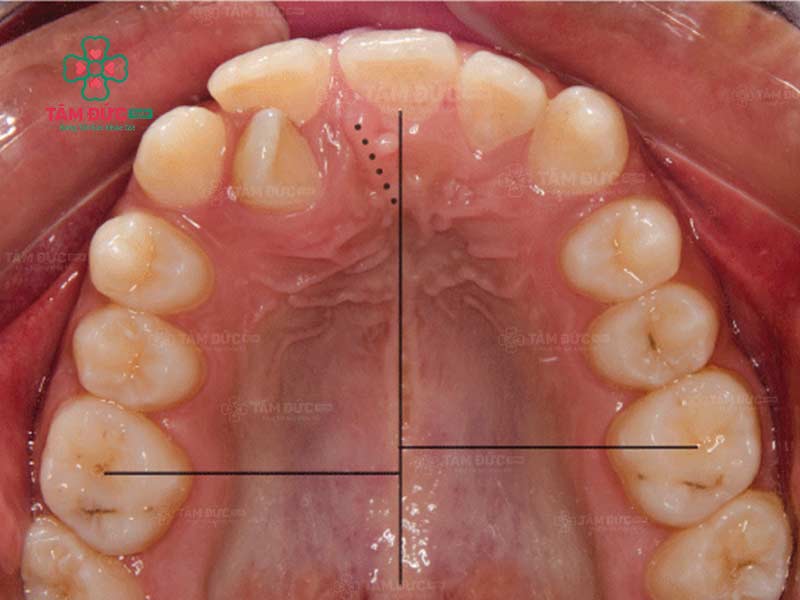

Răng lệch nhân trung là tình trạng kẽ giữa hai răng cửa không nằm thẳng với đường nhân trung. Đường nhân trung là một đường rãnh nhỏ nằm ở giữa mũi và môi trên. Ở người bình thường, kẽ giữa hai răng cửa sẽ nằm ngay trên đường nhân trung. Tuy nhiên, trong một số trường hợp, kẽ giữa hai răng cửa có thể lệch sang trái hoặc phải so với đường nhân trung.

Trường hợp bị lệch nhân trung